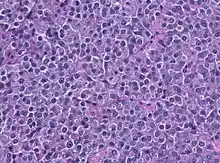

A prolactinoma is a tumor (adenoma) of the pituitary gland that produces the hormone prolactin. It is the most common type of functioning pituitary tumor.[1] Symptoms of prolactinoma are due to abnormally high levels of prolactin in the blood (hyperprolactinemia), or due to pressure of the tumor on surrounding tissues. Based on size, a prolactinoma can be classified as a microprolactinoma (<10 mm diameter) or a macroprolactinoma (>10 mm diameter).